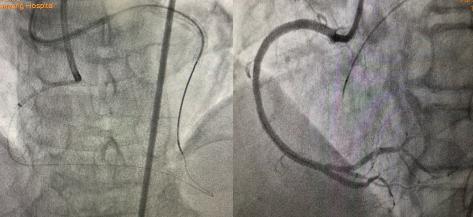

正向135cm1.8F微导管支持下再次尝试GAIA3、PILOT200仍失败,立即逆向送入150cm1.8F微导管至前降支远端,SION导丝塑小弯进入预先选择的间膈支,且顺利通过间隔支至右冠闭塞段远端,微导管亦顺利跟进至右冠闭塞段内。此时,逆向导丝如何进入正向导管内成为手术难题,既往多数病人皆因此而手术失败。此时手术团队利用AGT技术,正向指引导管内送入Guidezilla延长导管“出门迎客”,逆向微导管顺利进入正向延长导管,此过程历时约3分钟,至此预示手术基本成功,右冠成功开通。整个手术耗时70分钟,造影剂量150ml。

图2 AGT技术—正向Guidezilla延长导管成功迎接逆向微导管